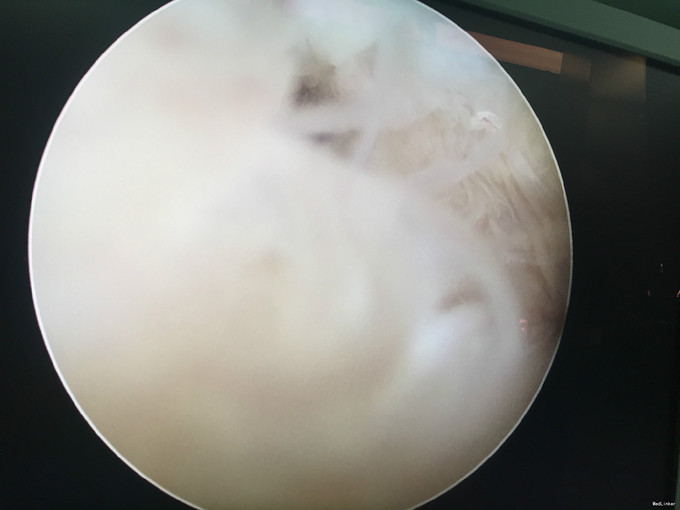

左膝扭伤后13年近1年反复不稳伴疼痛。 患者,男,39岁,13年前运动时扭伤左膝关节,当时未予重视,近1年出现左膝不稳伴疼痛,以上下楼、运动时明显,无法进行正常运动。遂于外院检查MRI(2015年3月)示:左膝关节退行性改变、左膝前交叉韧带信号异常、半月板信号异常、左膝关节内积液。为求进一步诊治来我门诊就诊,结合病史及体征,诊断“左膝半月板损伤、左膝前交叉韧带损伤”并收入院行进一步治疗。

入院诊断:左膝半月板损伤、左膝前交叉韧带损伤 治疗:入院后行左膝关节镜下外侧半月板成形+髁间窝成形+前交叉韧带自体肌腱重建手术。